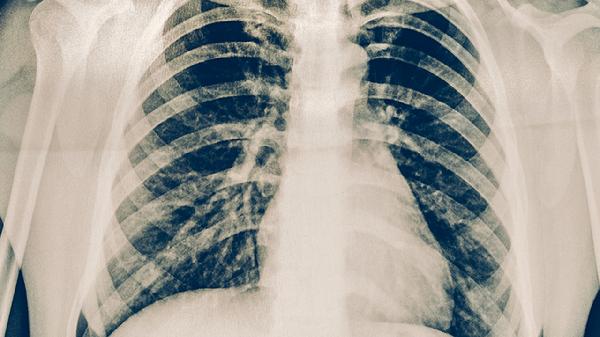

治療期間每月需進行痰涂片檢查直至轉陰,每2-3個月復查胸部X線評估病灶吸收情況。完成療程后仍需隨訪2年,第一年每3個月復查1次。出現(xiàn)咳嗽加重、咯血等癥狀需立即就診,警惕結核復發(fā)或耐藥可能。